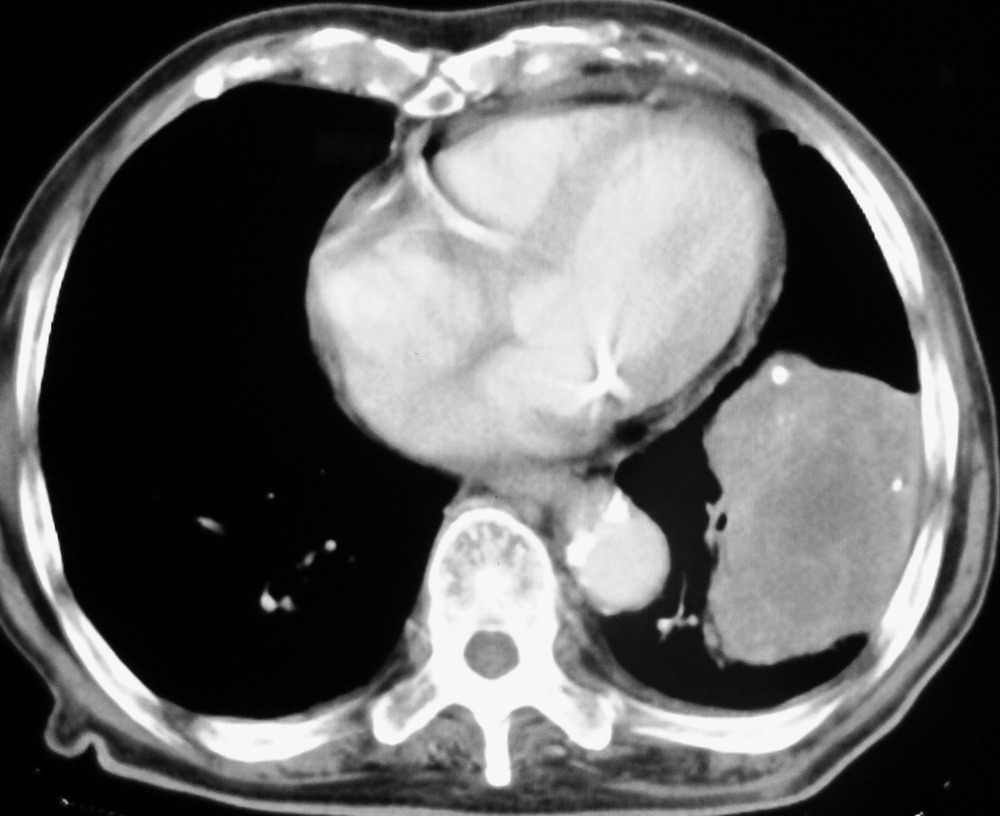

女,78,胸痛3个月,余无特殊。

肺癌,心包积液,右下胸膜肥厚。

1)左肺下叶软组织肿块,不排除周围型肺癌可能。2)左侧少量胸腔积液。3)心包积液。4)冠状动脉及主动脉钙化。

结果:肺癌